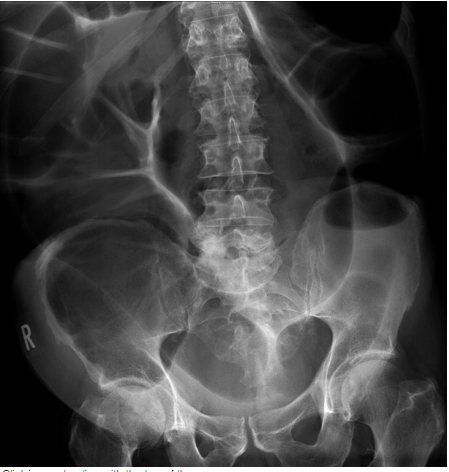

What does this AXR show?

Small bowel obstruction

• centrally localted multiple dilated loops of gasd filled bowel

• plicae are present confirming this is small bowel

• evidence of previous surgery- anastomes (red ring) - suggesting adhesions is the likely cause